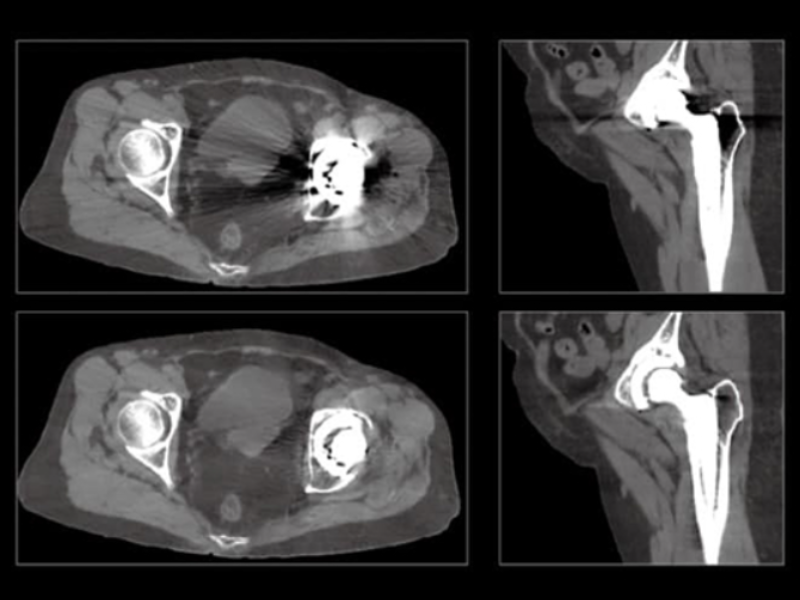

Metal Artifact Correction